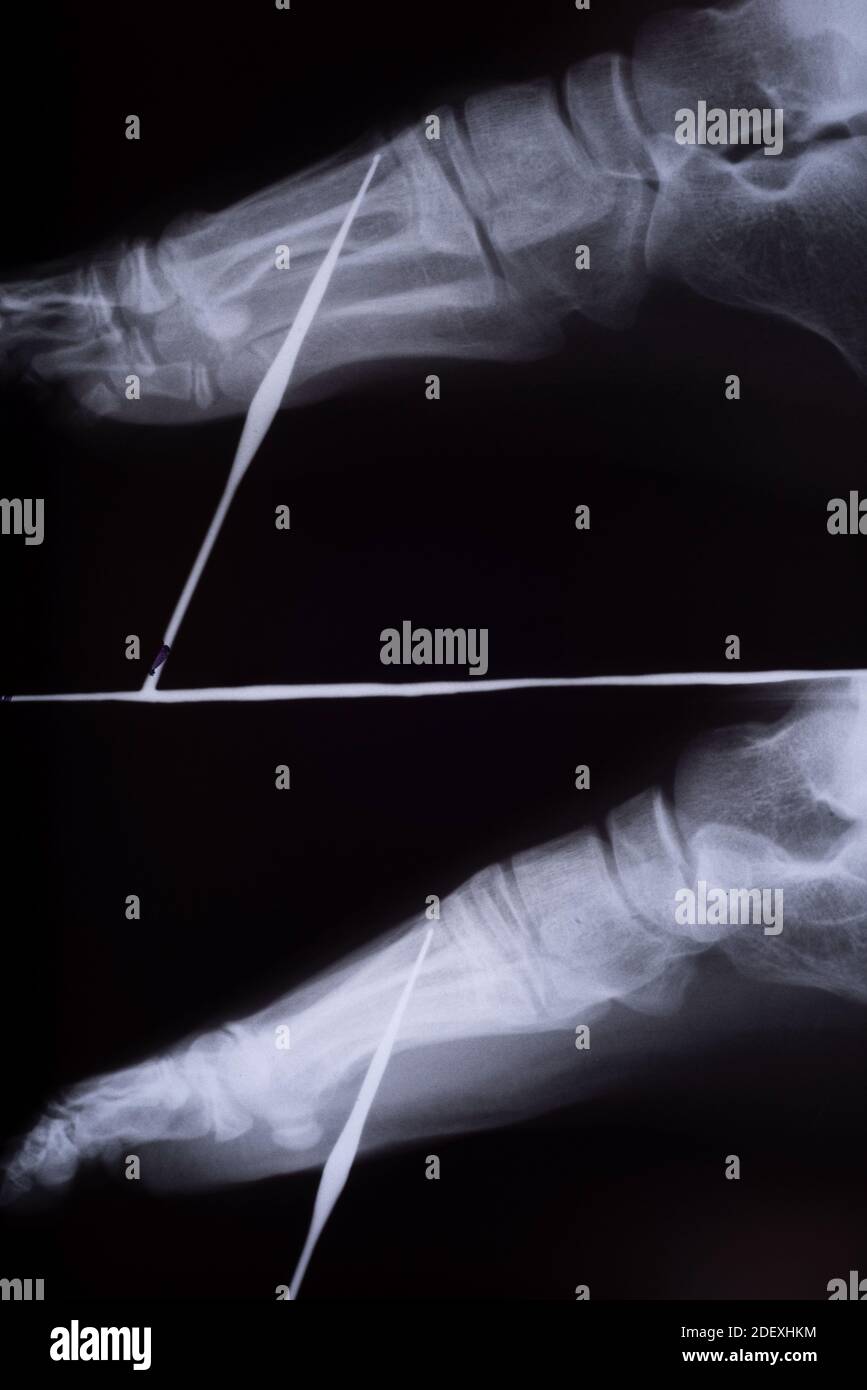

Nail in foot, Xray Stock Image C017/7980 Science Photo Library Nail In Foot X Ray The image displays the soft tissues and bones of your foot. The purpose of this review is to describe the anatomy of the nail unit, to become familiarized with the terminology used to describe the alterations of the ungual and the. Insert laminar spreaders and removed cartilage with curettes, osteotomes, drill with kwires to prep surface. 6 taking a thorough. Nail In Foot X Ray.

X ray nail Injury to foot Stock Photo Alamy Nail In Foot X Ray The image displays the soft tissues and bones of your foot. If the foot is over. Clinically, most puncture wounds initially appear benign, in the form of a small entry point with irregular skin margins and local ecchymosis. 6 delayed presentation can present with local edema, erythema, wound drainage, lymphadenopathy. Insert laminar spreaders and removed cartilage with curettes, osteotomes, drill. Nail In Foot X Ray.

Nail injury to foot, Xray Stock Image C038/6662 Science Photo Nail In Foot X Ray Insert laminar spreaders and removed cartilage with curettes, osteotomes, drill with kwires to prep surface. Timing of the injury is critical. Clinically, most puncture wounds initially appear benign, in the form of a small entry point with irregular skin margins and local ecchymosis. This view is useful in the assessment for joint abnormalities, determining the degree of dorsal or plantar. Nail In Foot X Ray.

foreign body foot xray of a child Xray radiograph image of a nail Nail In Foot X Ray 6 delayed presentation can present with local edema, erythema, wound drainage, lymphadenopathy. Timing of the injury is critical. This view is useful in the assessment for joint abnormalities, determining the degree of dorsal or plantar displacement in fractured bones, soft tissue effusions or gas. The purpose of this review is to describe the anatomy of the nail unit, to become. Nail In Foot X Ray.